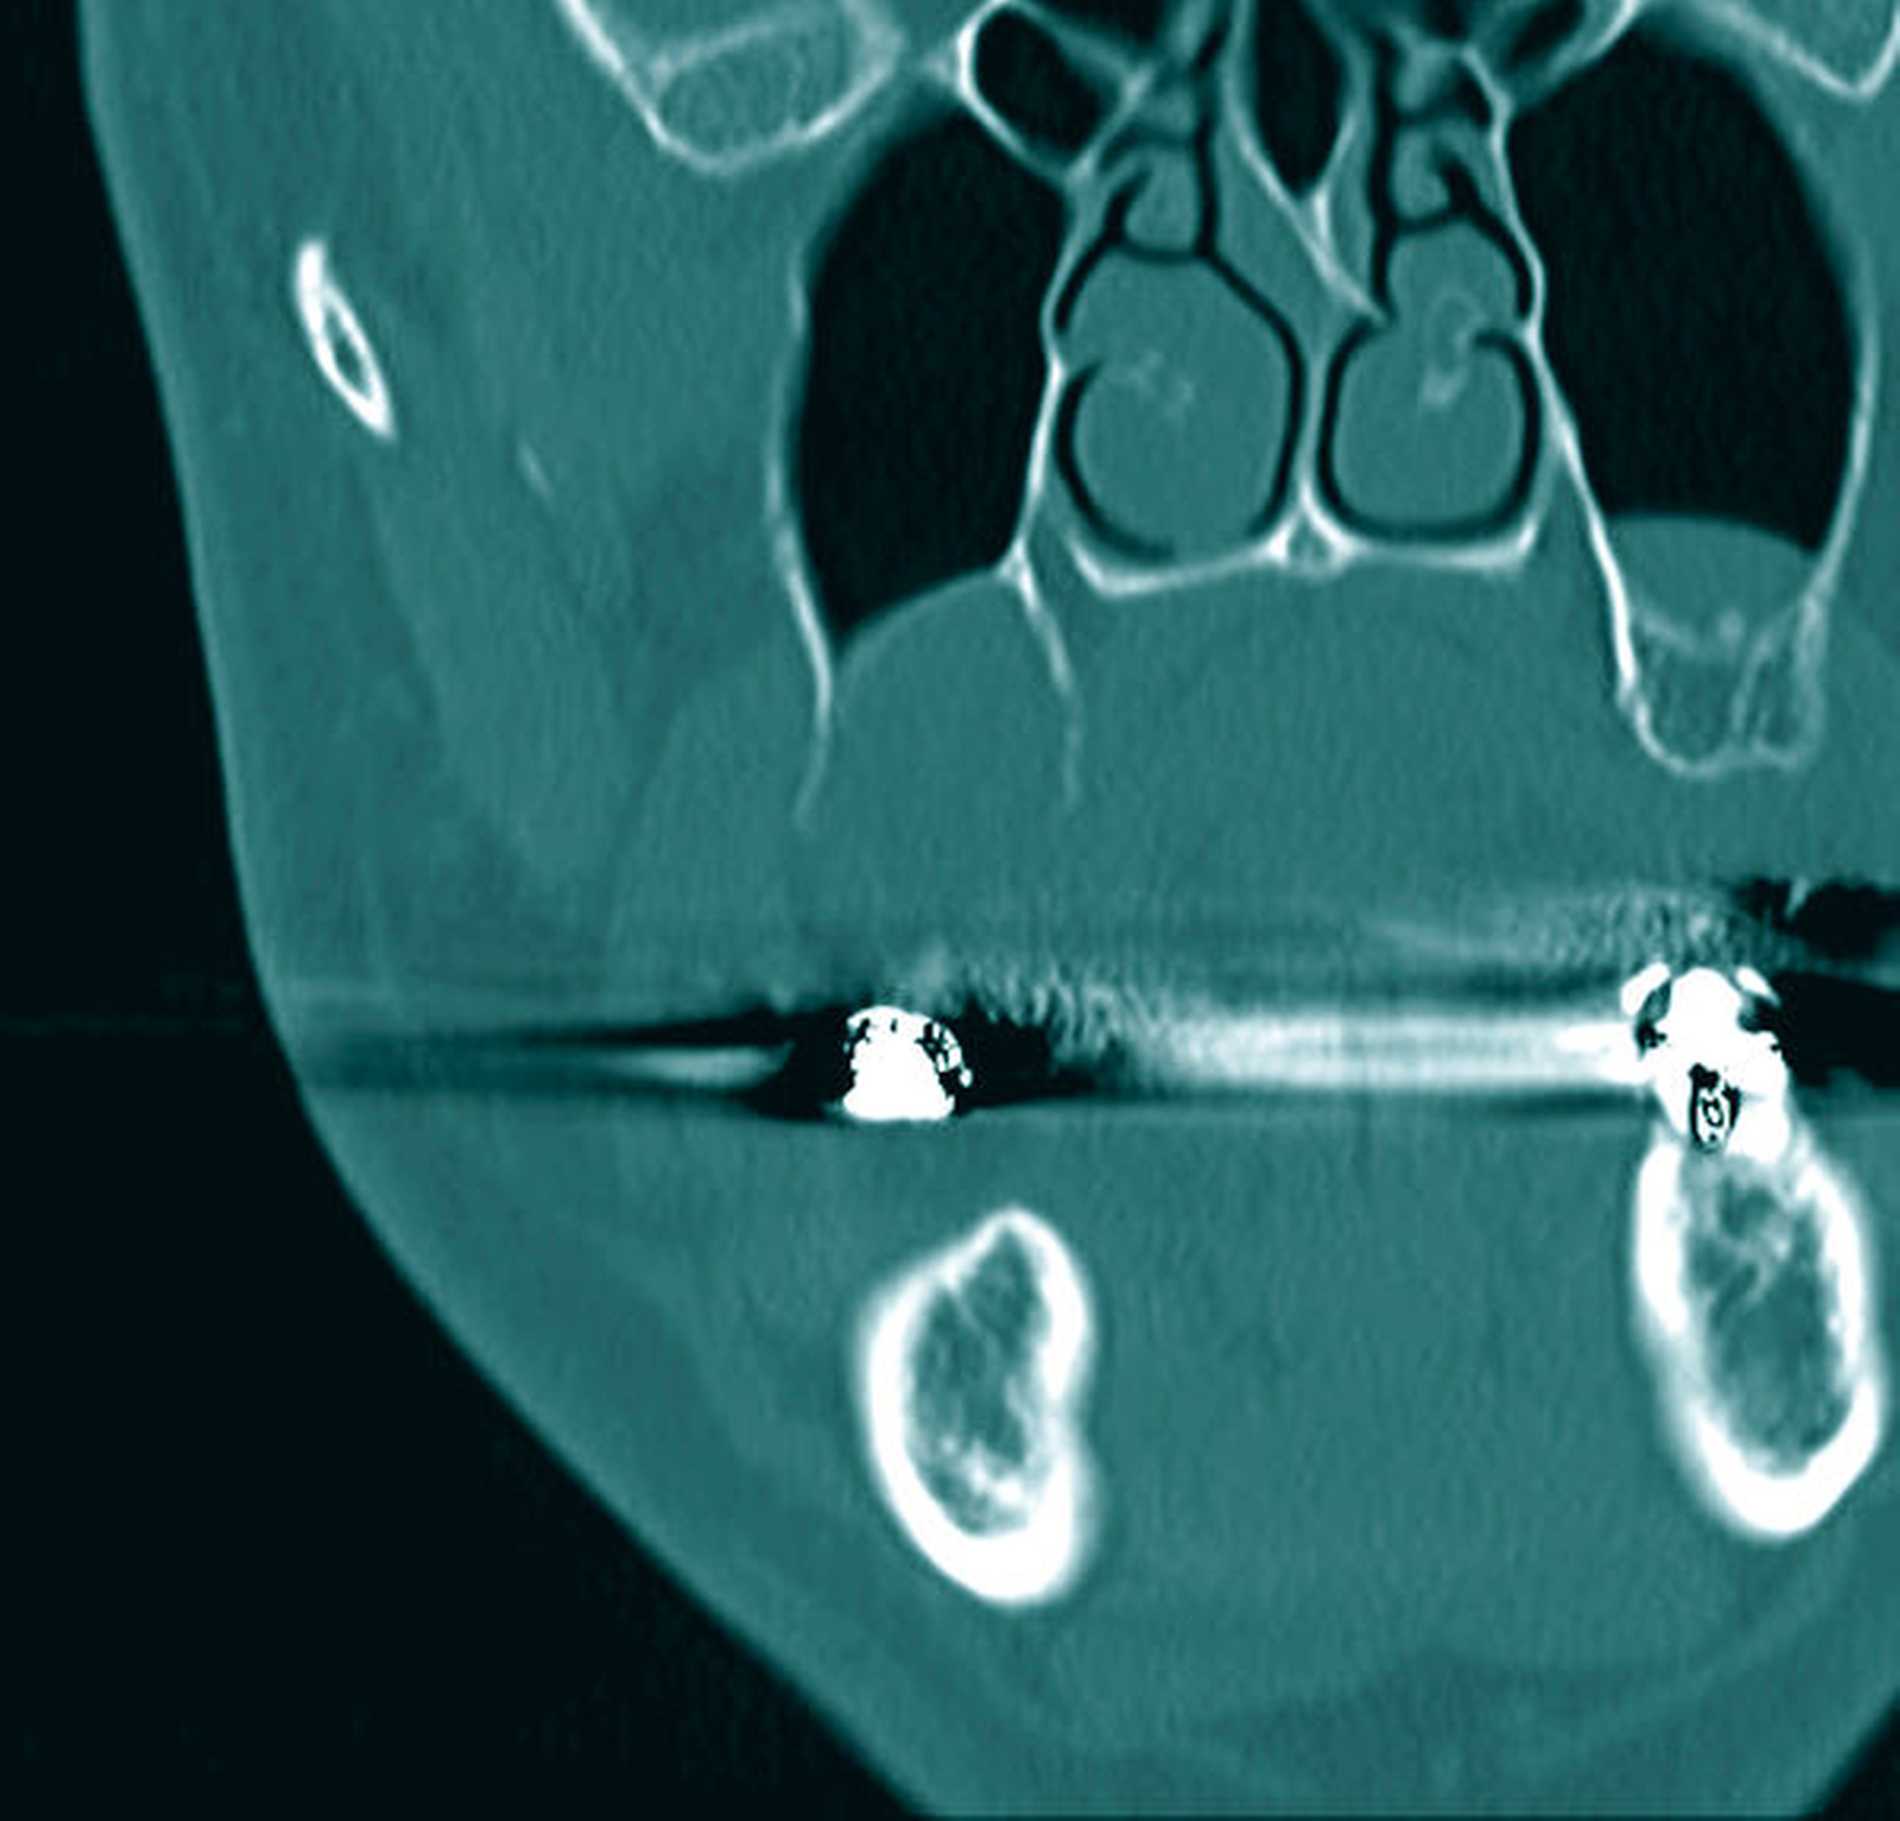

Ein 50-jähriger Patient ohne Nebenerkrankungen und Medikation stellte sich auf Überweisung seines Hauszahnarztes mit einem unklaren, tumorähnlichen Befund im rechten Oberkiefer vor. Intraoral zeigte sich vor allem distal des Zahns 17 eine fibrinbelegte, ulzerierend erscheinende Läsion. Die Zähne 17 und 16 reagierten negativ auf eine Vitalitätsprobe und wiesen einen Lockerungsgrad von I bis II auf. Insbesondere der Zahn 17 war mit seiner partiell freiliegenden Wurzeloberfläche auffällig (Abbildung 1). Eine Panoramaschichtaufnahme erbrachte den Nachweis einer starken Elongation des oberen, rechten zweiten Molaren mit erweiterten Parodontalspalt (Abbildung 2).